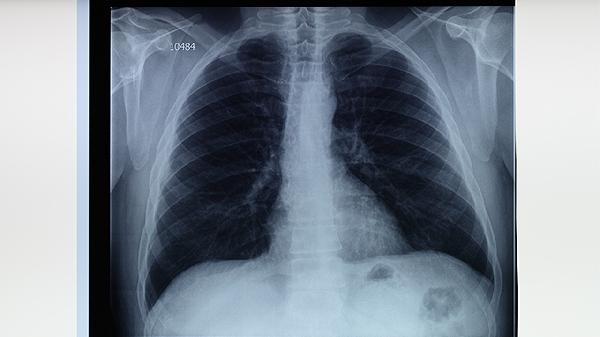

抗结核药物如异烟肼片、利福平胶囊、吡嗪酰胺片等能针对性杀灭结核菌,世界卫生组织推荐的标准短程化疗方案需持续用药6-9个月。治疗期间需定期复查痰菌、胸部影像学等指标评估疗效,中途擅自停用西药可能造成治疗失败。若患者对西药过敏或出现肝功能损害等情况,可遵医嘱调整方案并用中药辅助保护脏器功能。